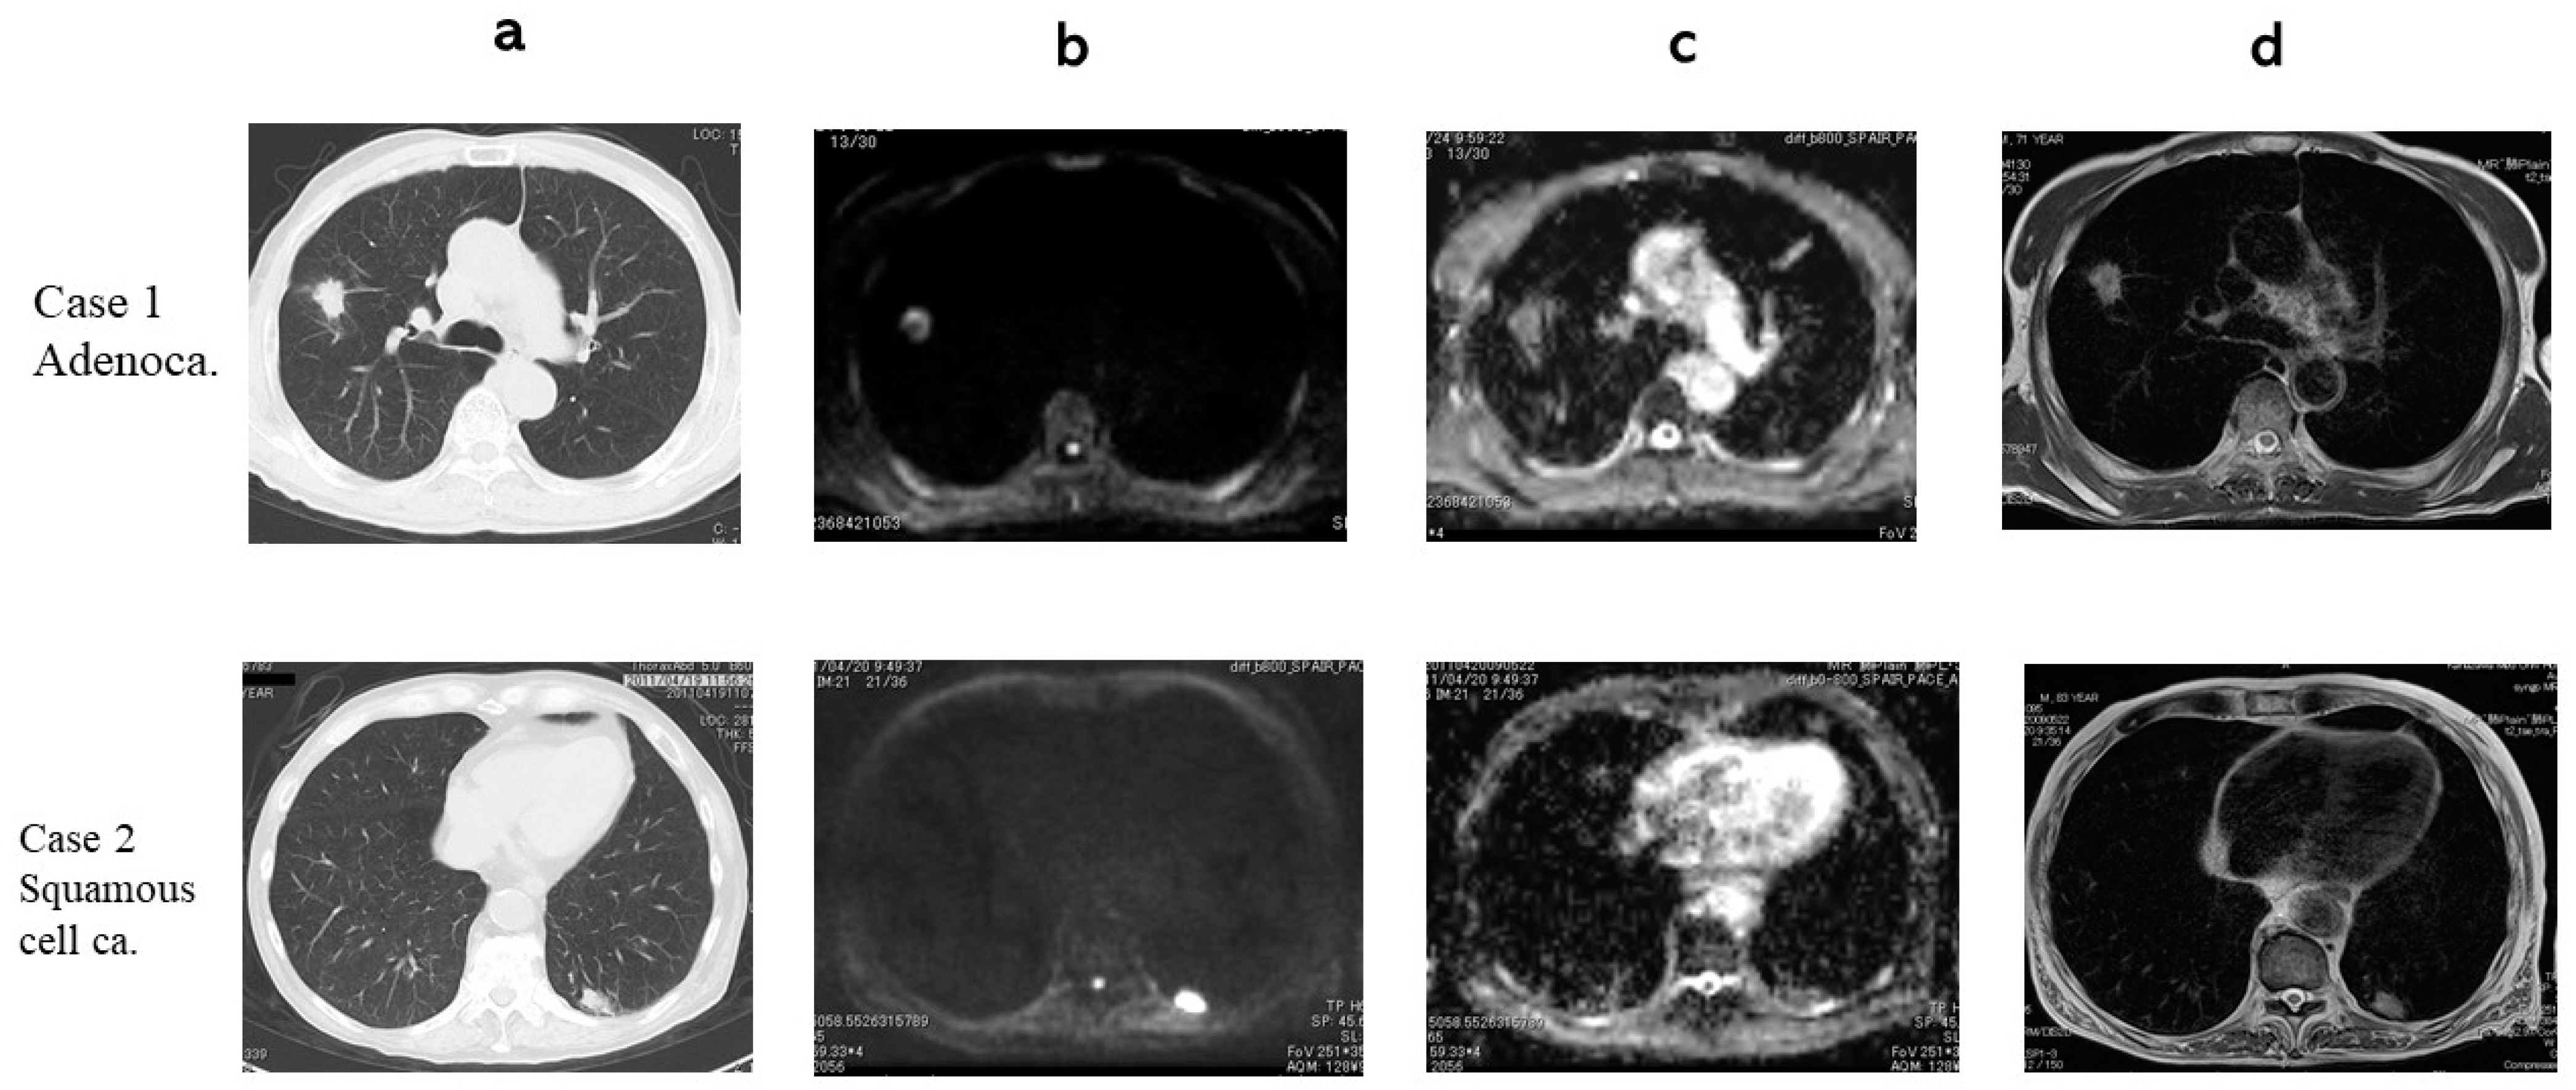

3. Results